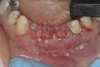

Two years later, however, the patient returned to her restorative dentist’s office complaining that “something felt different” on tooth No. 9. Localized moderate gingival inflammation was present on the facial aspect of No. 9 (Figure 12). A straight facial probing depth of 6 mm and severe bleeding on probing were also evident facially, suggesting a vertical root fracture.

Figure 12  Localized moderate gingival inflammation on facial aspect of No. 9 (2 years post-cementation).

Figure 12